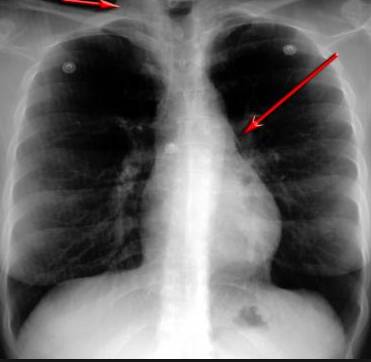

并且,因為呼吸系統(tǒng)結(jié)構(gòu)復雜,在體檢時醫(yī)生很難通過一種檢測手段,判定早期患者的病情。

所以,很多人發(fā)現(xiàn)自己得了肺病,哮喘或其他呼吸系統(tǒng)疾病的時候,已經(jīng)很危險了!多少人因此錯過最佳治療期!

能讓醫(yī)生有一雙可以透視的眼睛

把整個肺部看得清清楚楚!

使用這臺掃描儀,將直接把器官變成3D圖形!細微的毛細血管,幾毫米大的肺泡和支氣管,都將能看的一清二楚!

你的每一個氣泡,每一段支氣管,哪兒有病變都清清楚楚的將展示在醫(yī)生面前!

也就是說在一切都還沒開始惡化前,把這些有問題的器官組織都暴露的一清二楚:

沒有這項新技術(shù),醫(yī)生在做體檢的時候,很難通過一種測試斷定一個人是否有呼吸系統(tǒng)疾病。

可是現(xiàn)在他們不但能看到整個肺部的3維結(jié)構(gòu)圖。還能看到空氣進入人體后的所有微小變動!